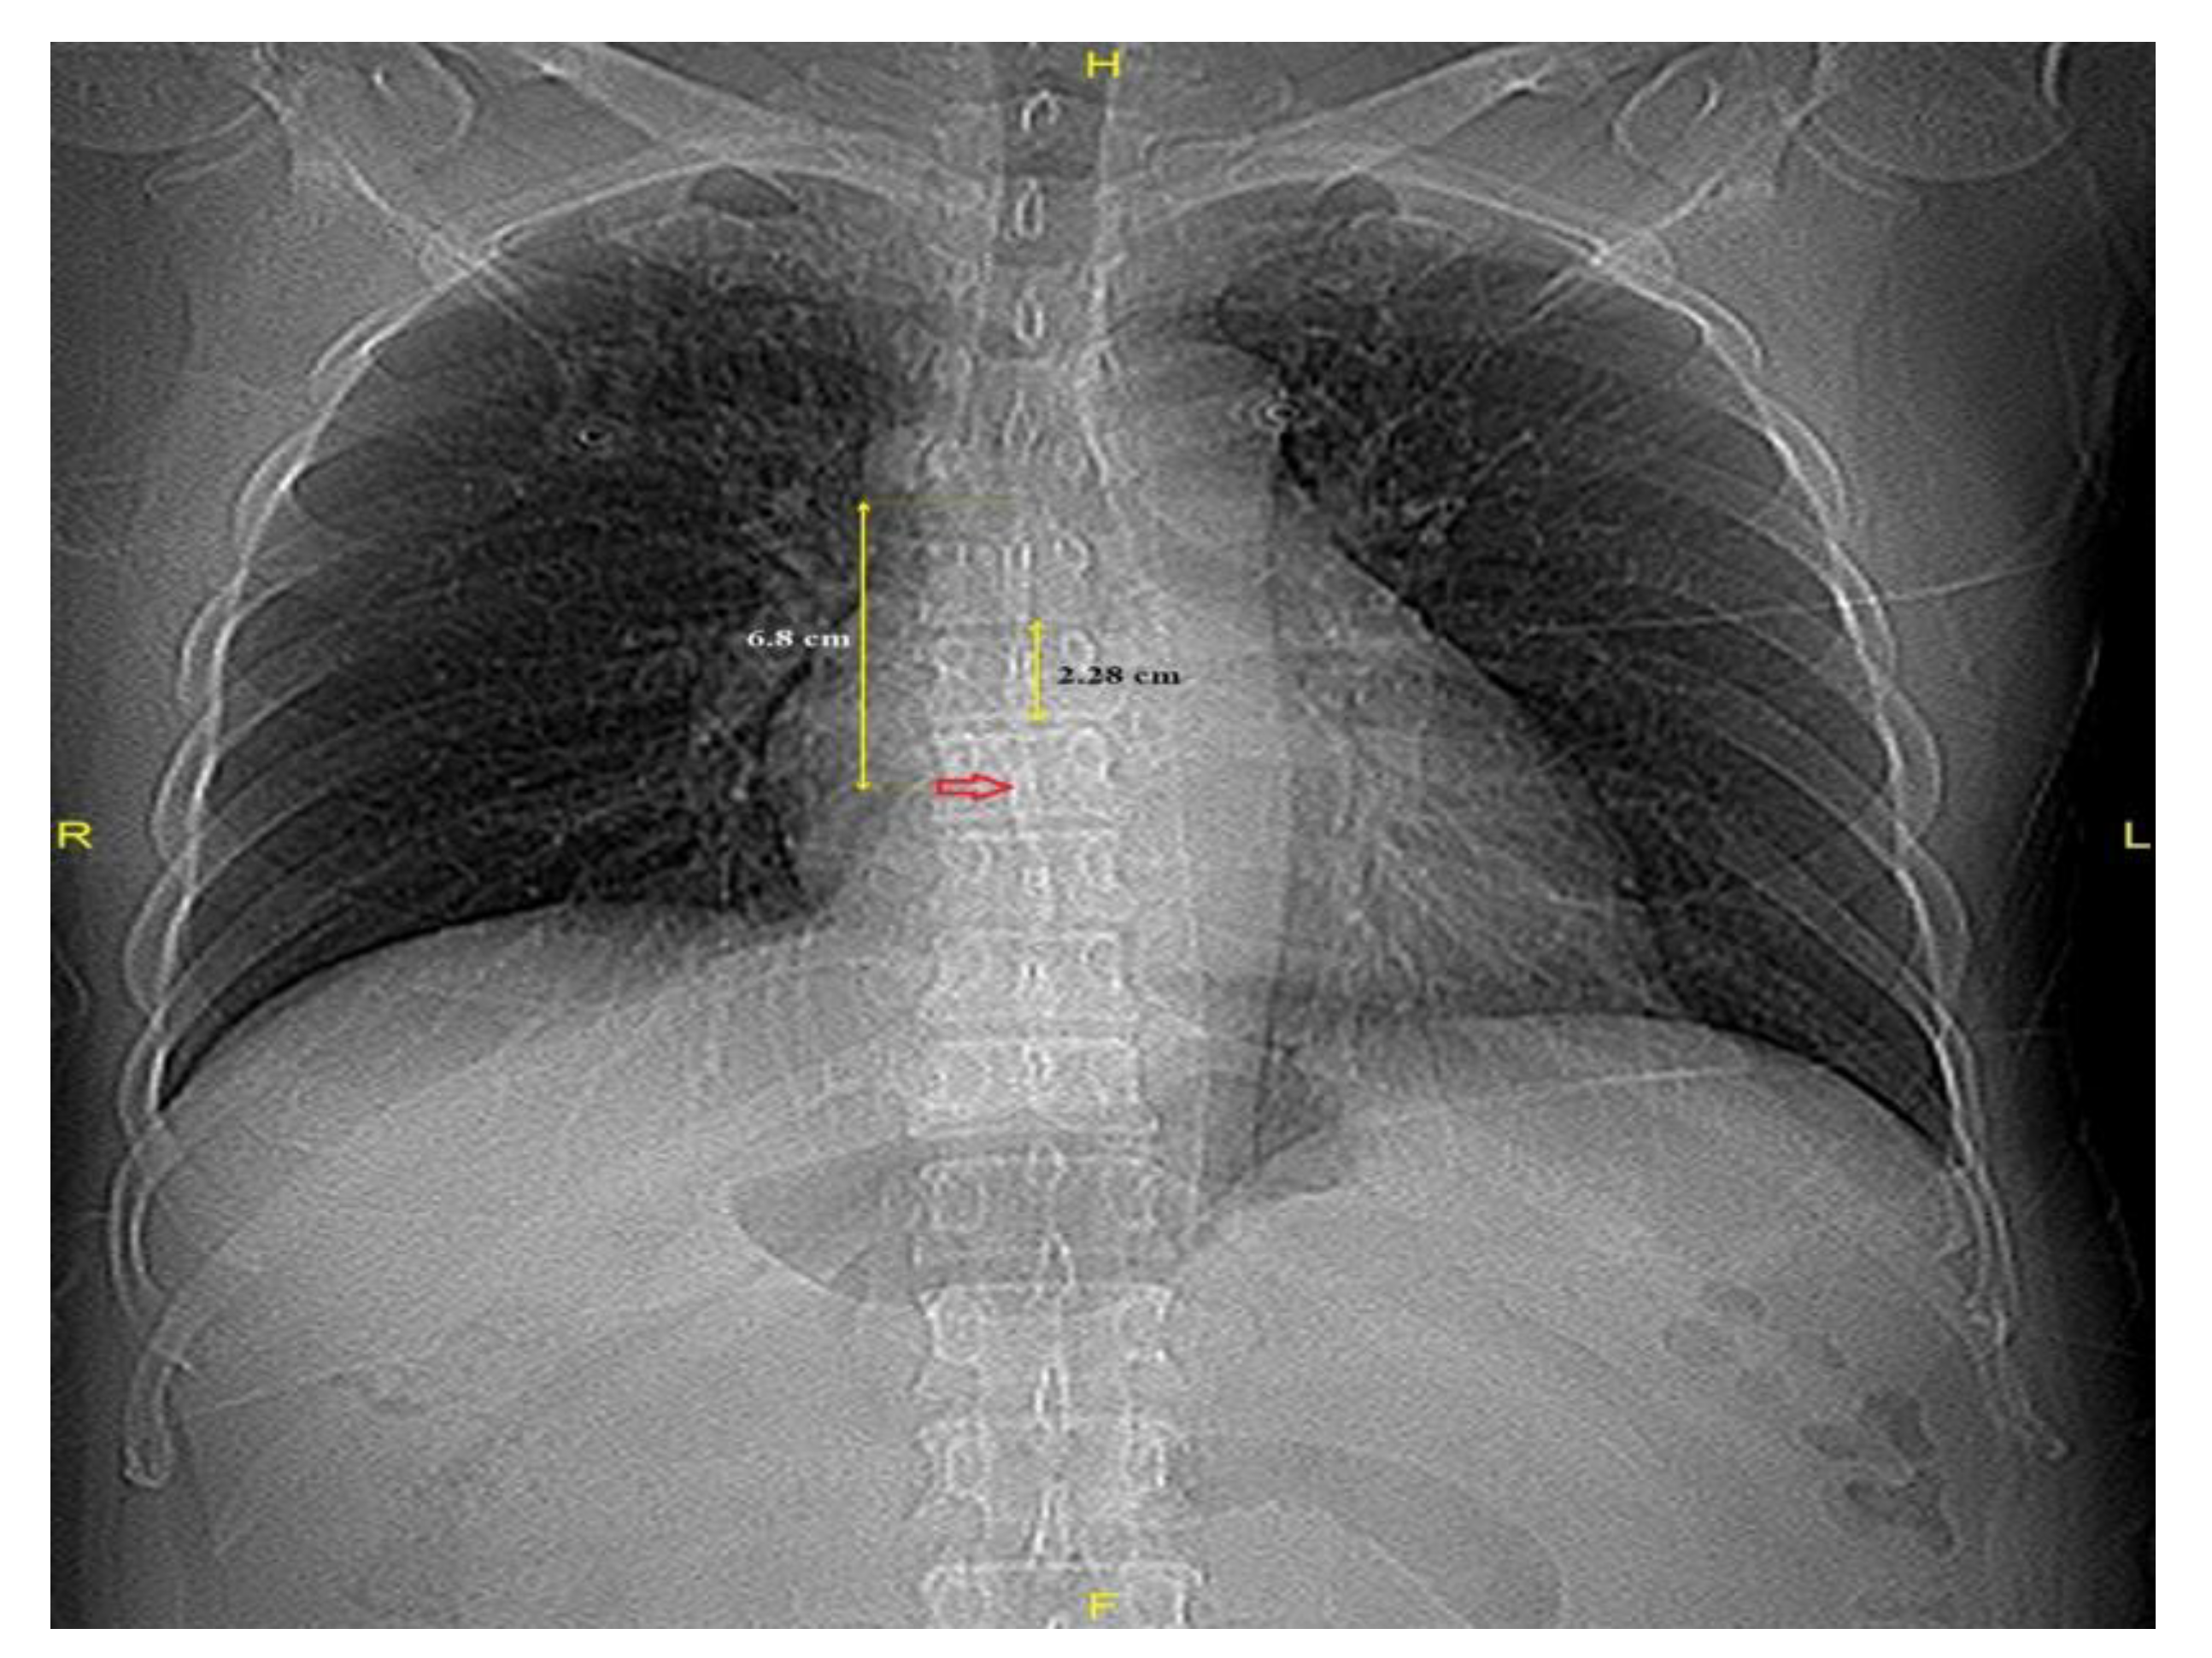

2.3. Image Acquisition and Measurement

| Carina–FO (cm) | 6.8 ± 0.8 | 7.3 ± 1.2 | 7.5 ± 0.7 | <0.001 |

| Carina–FO VBU−1 | 3.0 ± 0.3 | 3.1 ± 0.4 | 3.2 ± 0.4 | 0.001 |